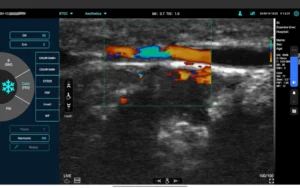

Szkolenie z zakresu zakresu anatomii oraz ultrasonografii obejmuje nowoczesne metody pracy w gabinecie ze skórą w ujęciu anatomicznym. Kurs obejmuje zarówno wiedzę teoretyczną jak i praktyczną. W czasie kursu zostaje przekazana wiedza anatomiczna, która przydatna jest zarówno przy zabiegach kosmetologii estetycznej takie jak mezoterapia igłowa czy stymulatory tkankowe.. Dodatkowo zastosowanie USG pozwoli nam zajrzeć głębiej we warstwy skórne i zobrazować możliwości zabiegowe.

- Omówienie aparatu USG oraz podziału głowic.

- Podstawowa terminologia obejmująca echogeniczność, hiperechogeniczność, hipoechogeniczność i anechogeniczność.

- Zastosowanie głowicy przy zabiegach.

- Praca z ultrasonografem.